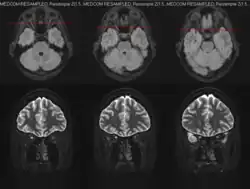

MRI

Magnetic resonance imaging (MRI) is a robust and sensitive diagnostic modality for the detection of optic neuritis. Imaging of the optic nerve with MRI shows increased signal on the affected side. There is contrast enhancement of the symptomatic optic nerve and sheaths acutely or intrinsic signal increase (looking brighter) within ≥ 3 months. One study found that MRI of the orbits with fat suppression and gadolinium enhancement detected acute optic neuritis lesions in 95% of affected individuals within 20 days of vision loss.[23] Another study found that T2-weighted images with fat suppression and short tau inversion recovery (STIR) detected lesions in up to 89% of acute optic neuritis cases with abnormalities persisting for as long as 6 weeks in 92% of cases.[24]

Identification of optic nerve, orbital, brain, and meningeal involvement with MRI can also help to better characterize the underlying cause of optic neuritis upon initial evaluation. Unilateral optic nerve involvement is more common MS while bilateral optic nerve involvement is more common in NMOSD and MOGAD.[7] T2-hyperintense and gadolinium-enhancing lesions in multiple regions of the brain and/or spinal cord may be highly suggestive or diagnostic of MS. Such lesions found in the periependymal, fornix, and hypothalamic lesions may be more suggestive of NMOSD.[7] Involvement of the optic chiasm or optic tract are more suggestive of NMOSD-optic neuritis; involvement of the retrobulbar optic nerve can be seen in both NMOSD and MOGAD, but more commonly in MOGAD; perineural optic nerve involvement is often suggestive of MOGAD-optic neuritis, but should not preclude the investigation of other autoimmune or infectious etiologies.[7]